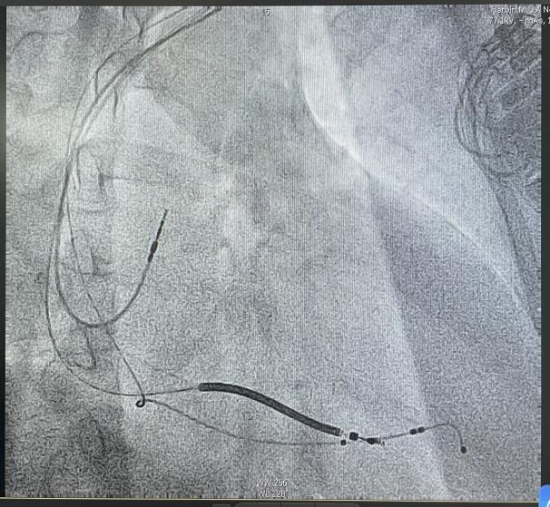

术中,造影显示患者冠状静脉靶血管直径粗且走行平直,若采用传统被动固定左室电极,不仅难以精准定位起搏靶点,术后电极脱位风险也显著升高,还可能增加术后CRT无应答风险。为追求更优的手术效果、提升患者长期预后,曹雪教授团队决定为患者采用新型左室主动固定四极电极实施CRTD植入术。该新型主动电极配备了侧螺旋固定装置,可以主动旋入血管壁,不仅能突破血管形态限制,精准选择最优起搏靶点,最大化改善心脏再同步化效果,大幅提升患者术后治疗反应率,更显著降低了术中术后电极脱位的风险,为患者长期稳定的疗效提供了坚实保障。

手术由曹雪主任医师和孙丽秀副主任医师实施,团队成员默契配合,术中精准完成冠状静脉造影定位,凭借丰富的介入操作经验,顺利将左室主动电极通过侧螺旋固定模式,精准植入到最优起搏靶血管位置,完成左室电极的植入与固定。经牵拉、推动测试,电极稳定性极佳,起搏阈值、感知、阻抗等各项参数均达理想标准。术后患者心脏电同步性显著改善,无任何手术并发症,各项生命体征平稳,心衰相关症状明显改善。

术后影像